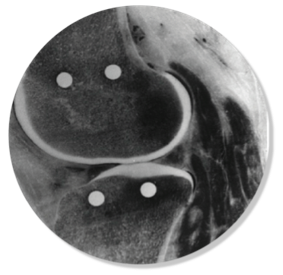

Question 5

Question

Which implant is shown in this image

Answer

• ZUK

• Cambridge

• Oxford

Question 6

How would you describe this implant?

• Fixed bearing unicompartmental

• Mobile bearing unicompartmental

• Fixed bearing total knee

• Mobile bearing total knee

Question 7

Which compartment is shown

• Trochlear

• Medial

• Lateral